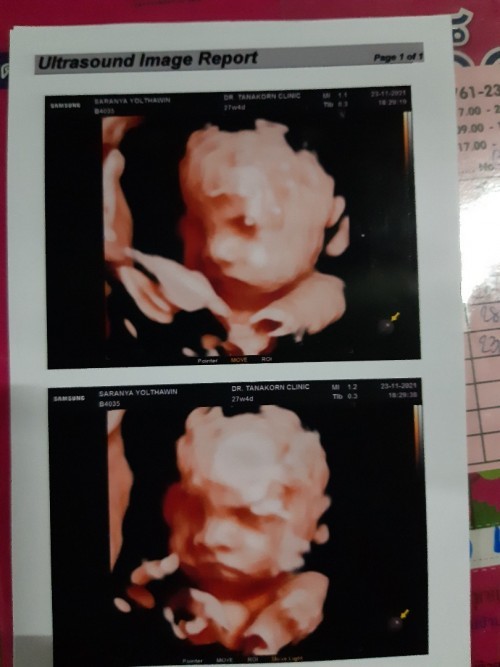

ท้องแรกค่ะ 👧🏻 กำหนดคลอด19ก.พ.65